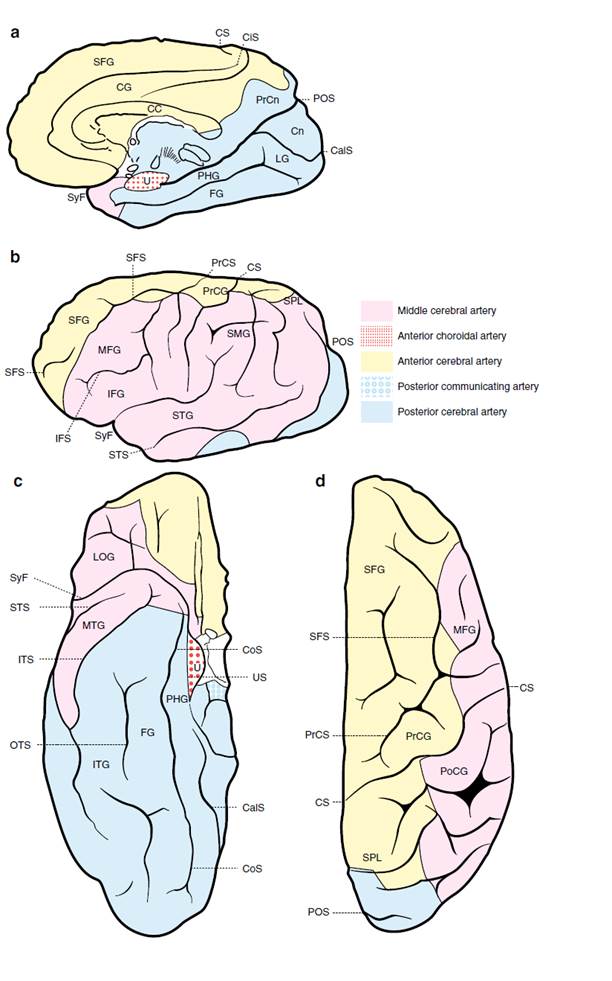

Cerebral vascular territories